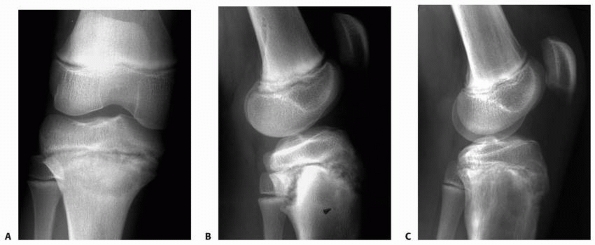

| Figure 5-10 Stress injury of the proximal tibia in an elite soccer player. A. Anteroposterior radiograph film demonstrates subtle proximal tibial physeal widening. B. Lateral radiograph shows widening, a metaphyseal Thurston-Holland fragment, and some posterior displacement of the proximal epiphysis. C. Significant radiograph improvement noted after discontinuing athletic activities for 3 months. |